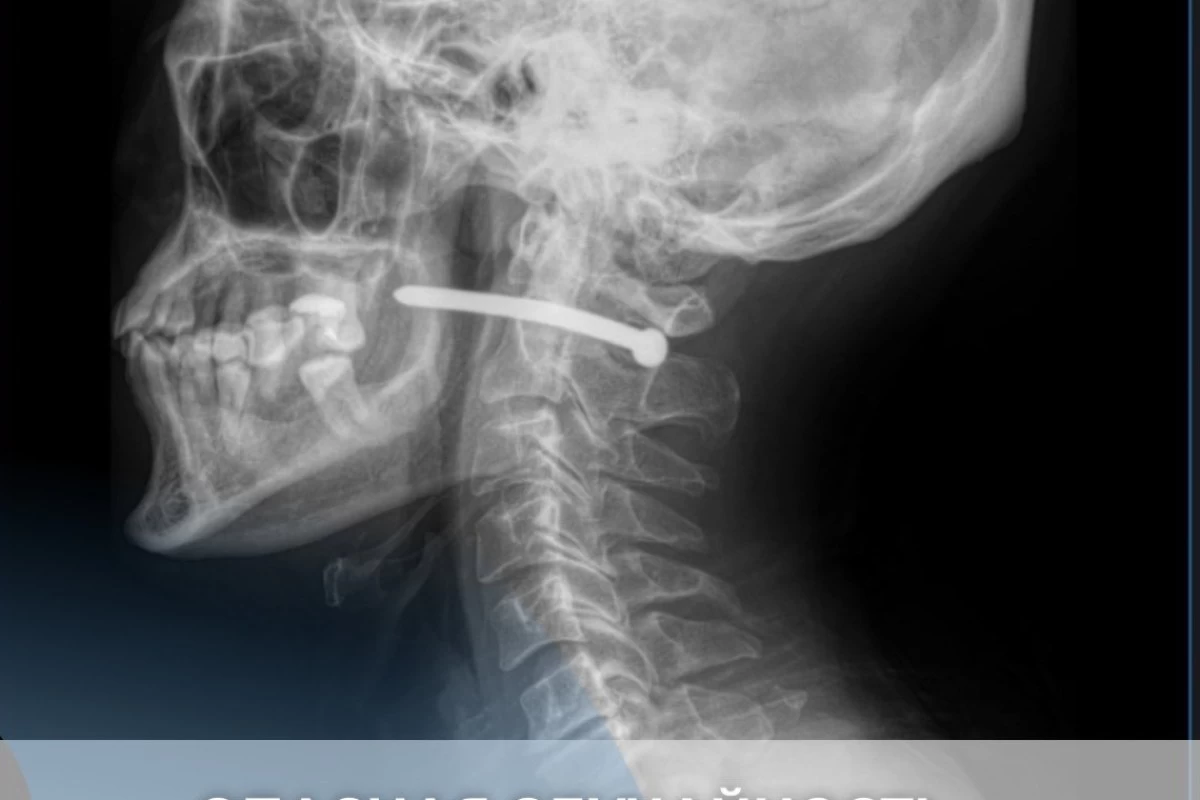

ер адамның мойнына шеге кіргенФото: kbka.sko.kz

Қалалық көпсалалы жедел жәрдем ауруханасының мәліметінше, 51 жастағы ер адам ауруханаға құлағының артындағы жарақатымен түскен. Жөндеу кезінде ол байқаусызда пневматикалық тапаншадан жарақат алған. Рентген нәтижесінде шегенің мойын омыртқасы маңынан өткені анықталған.

"Ер адам таңғажайып жағдайда аман қалды. Оның өмірлік маңызы бар ағзалары зақымданбады. Жақ-бет хирургтары шегені алып, жараны тазалап, тігіп шықты. Стерильді таңғыш қойылғаннан кейін науқасқа тиісті нұсқаулар беріліп, үйіне жіберілді", – делінген хабарламада.